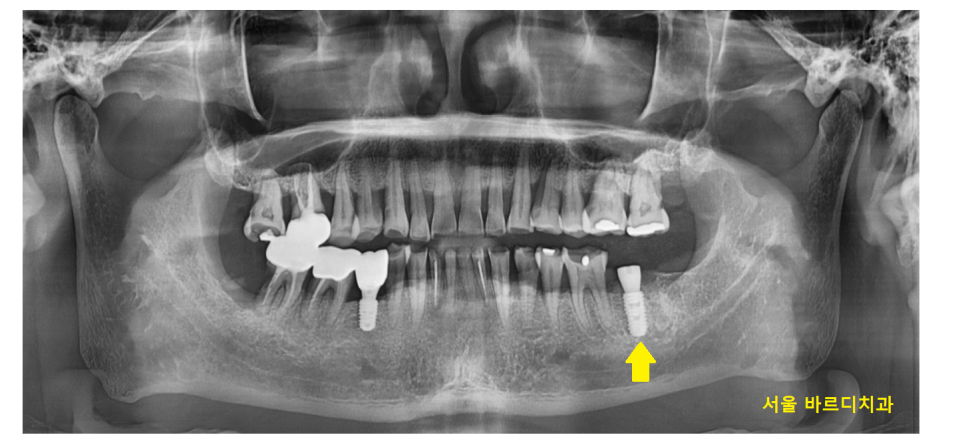

23.10.10

저희 병원을 처음 내원해주셨을 때

사진만 보고도 치아가 많이 닳으셨겠구나

보이더라고요.

23.10.16

어금니 금감 발치 후

풍산동 임플란트 진행했습니다.